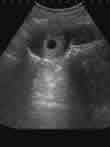

怀孕在5周-8周,胎儿和胎盘尚未形成,一般不需要扩张宫颈,是进行人流的最佳时机.